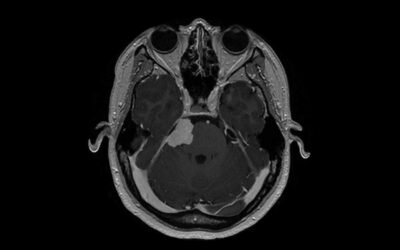

Meningiomas are associated with some birth control

Several recent studies point to an increased risk that women have of developing a meningioma when using injectable birth control. But only a total of about 50,000 people in the U.S. are diagnosed with this type of brain tumor each year. “While this is certainly the...

NBC News ft. David Raleigh – Is Depo-Provera birth control to blame for this woman’s brain tumor

Read and Watch the latest NBC News special on whether the birth control shot caused their meningiomas, a tumor that grows from the lining of the brain. A lawsuit alleges Pfizer failed to warn of potential risk. UCSF Radiation Oncology faculty Dr. David Raleigh, weighs...